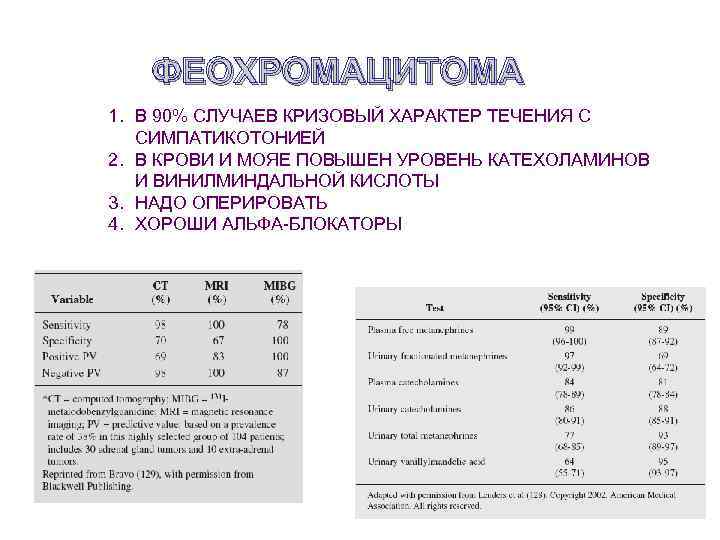

ФЕОХРОМАЦИТОМА 1. В 90% СЛУЧАЕВ КРИЗОВЫЙ ХАРАКТЕР ТЕЧЕНИЯ С СИМПАТИКОТОНИЕЙ 2. В КРОВИ И МОЯЕ ПОВЫШЕН УРОВЕНЬ КАТЕХОЛАМИНОВ И ВИНИЛМИНДАЛЬНОЙ КИСЛОТЫ 3. НАДО ОПЕРИРОВАТЬ 4. ХОРОШИ АЛЬФА-БЛОКАТОРЫ

ФЕОХРОМАЦИТОМА 1. В 90% СЛУЧАЕВ КРИЗОВЫЙ ХАРАКТЕР ТЕЧЕНИЯ С СИМПАТИКОТОНИЕЙ 2. В КРОВИ И МОЯЕ ПОВЫШЕН УРОВЕНЬ КАТЕХОЛАМИНОВ И ВИНИЛМИНДАЛЬНОЙ КИСЛОТЫ 3. НАДО ОПЕРИРОВАТЬ 4. ХОРОШИ АЛЬФА-БЛОКАТОРЫ